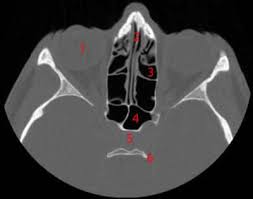

Os pedidos de exames TAC (Tomografia Axial Computorizada) e de sessões de fisioterapia nos centros privados convencionados estão agora mais difíceis para os doentes do Serviço Nacional de Saúde (SNS). O ministro Paulo Macedo quer racionalizar os exames médicos, que passam a ficar sujeitos à emissão de um termo de responsabilidade autorizado pelo conselho clínico do agrupamento dos centros de saúde (ACES), segundo um despacho ontem publicado em Diário da República.

O Hospital de Santa Maria, em Lisboa, tem cerca de dois mil doentes em lista de espera para fazer uma Tomografia Axial Computorizada (TAC), e o Hospital Pulido Valente tem duzentos doentes a aguardar. A maior parte são doentes oncológicos. O aumento das listas parece ser o resultado mais imediato do despacho de Agosto do ministro Paulo Macedo que corta exames no sector privado e que está a deixar as unidades públicas de saúde sem capacidade de resposta.